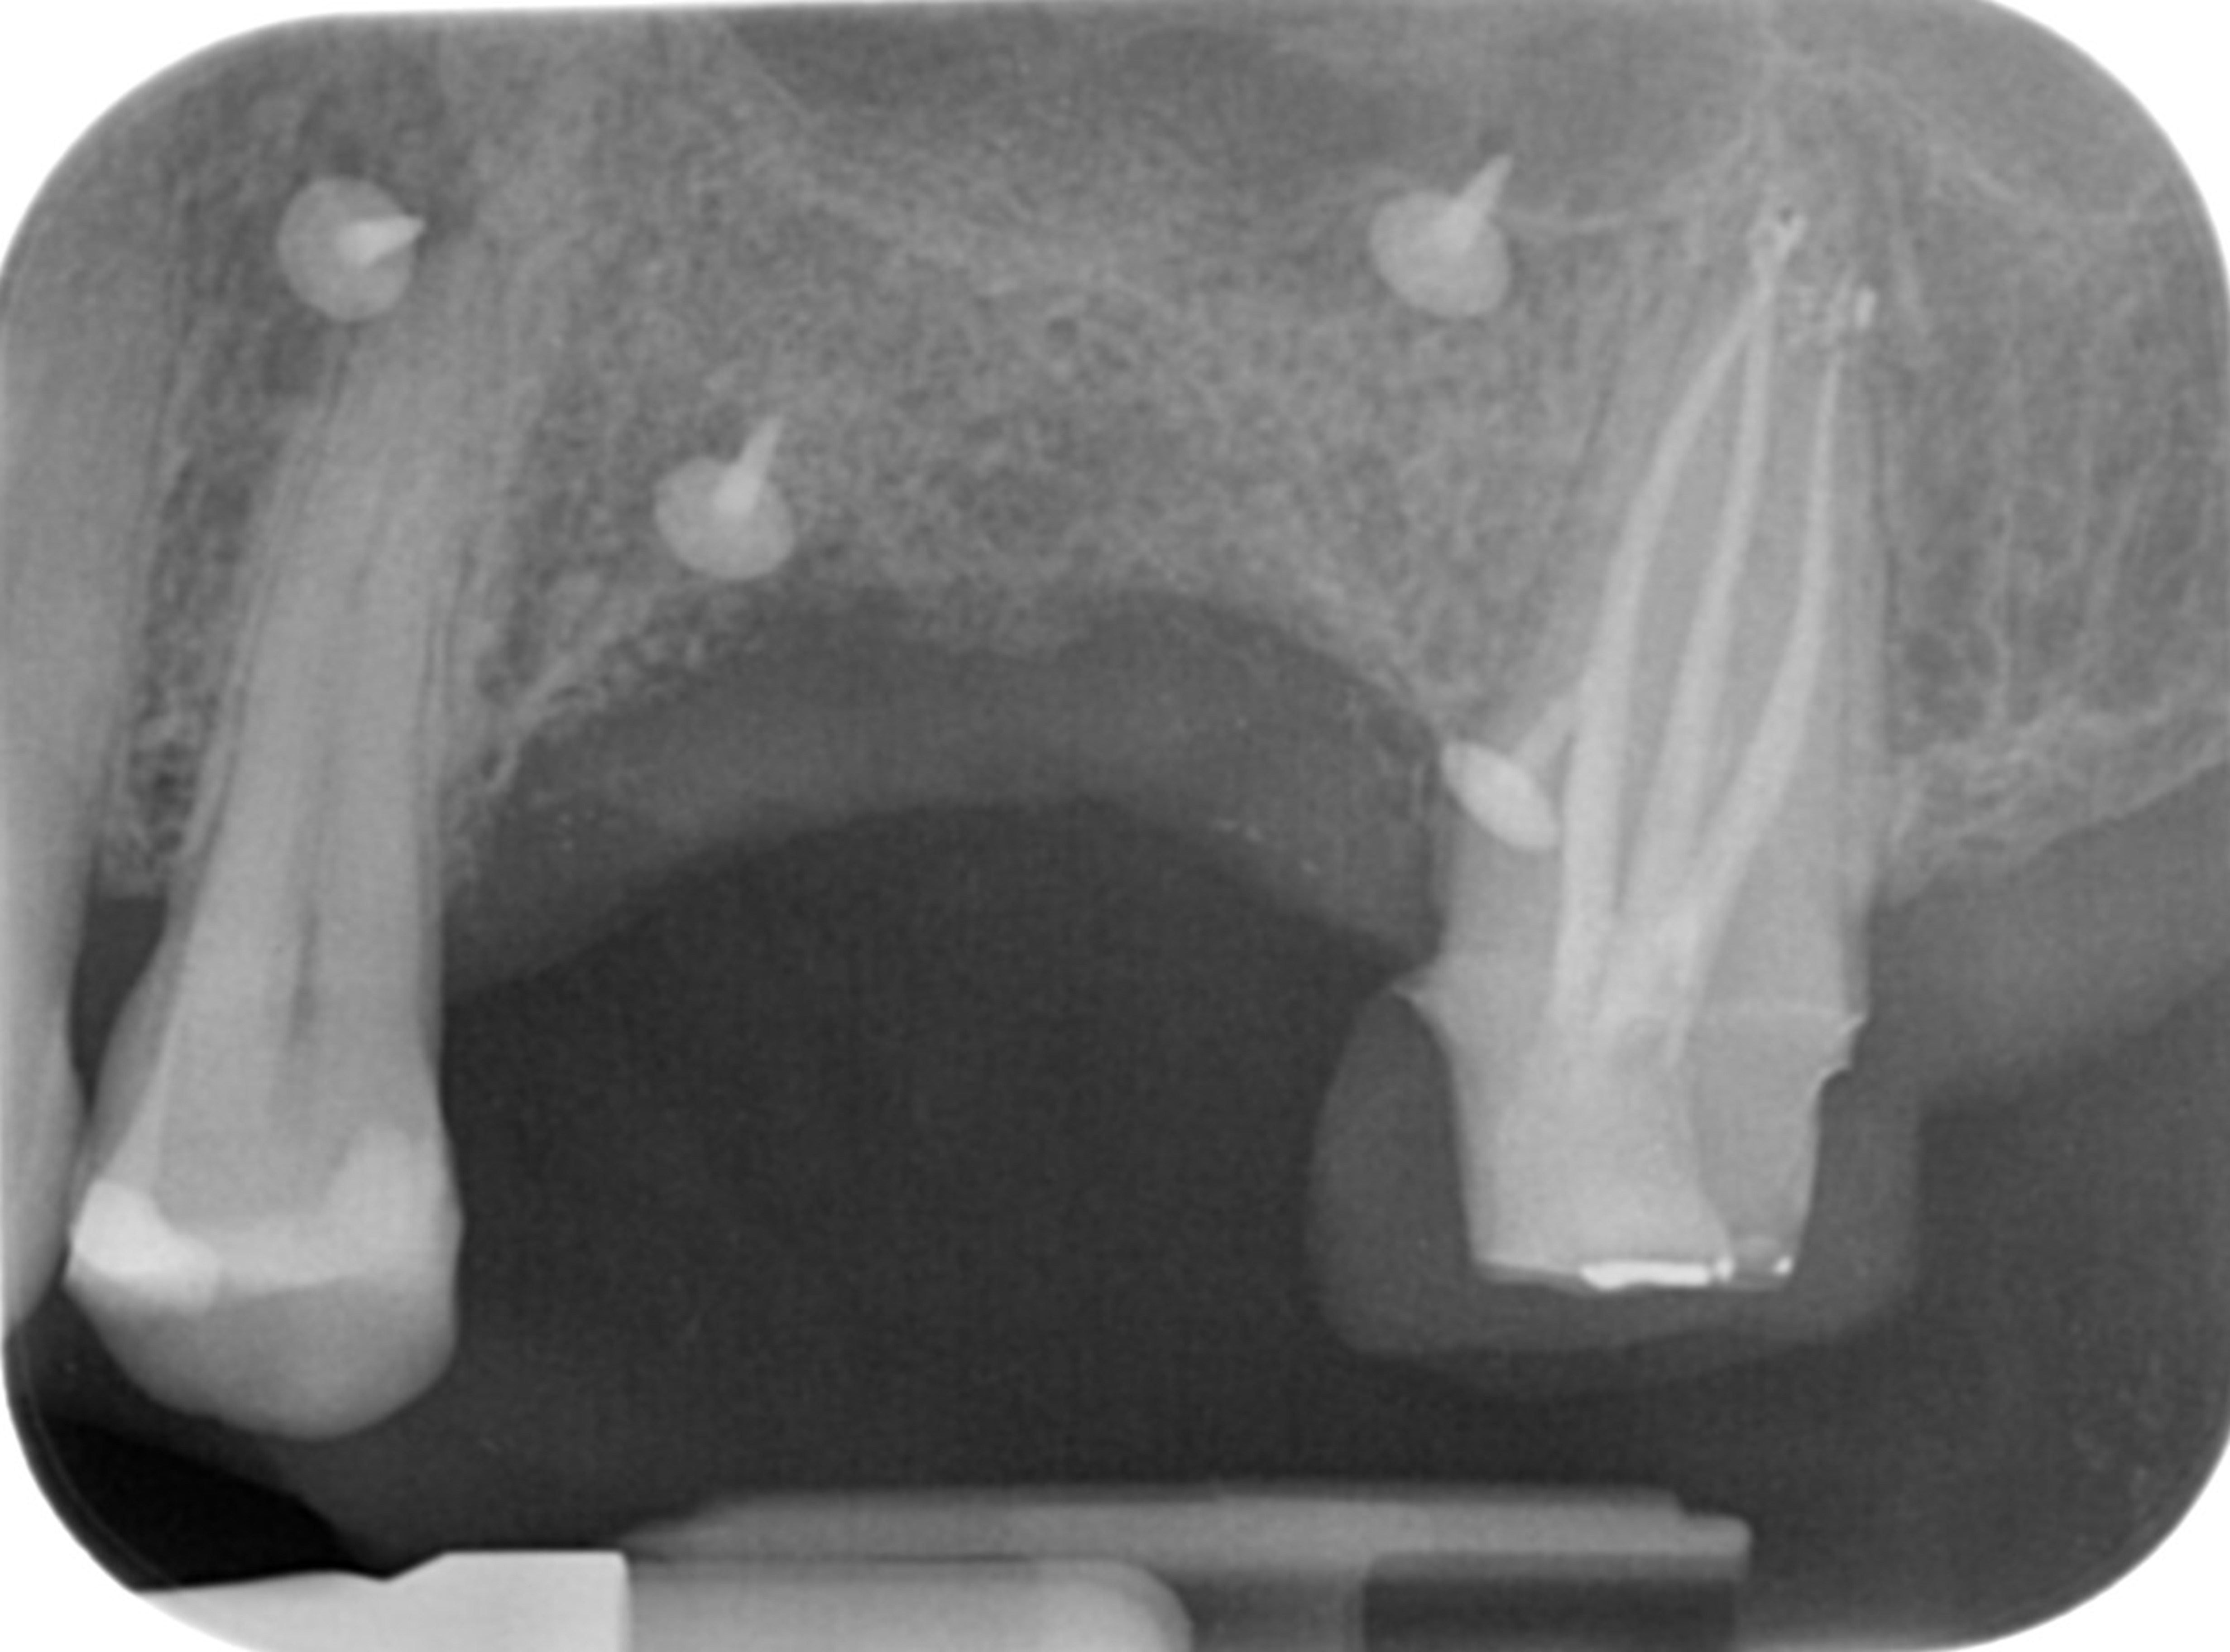

Female patient, 53 years old. She came to our attention for a problem related to a three-element bridge in zone 25-26-27. The intraoral examination was diagnosed with the unrecoverability of element 2.4, the need for root canal therapy of 2.7, and considerable horizontal bone resorption in the 26 sites.

Removal of the prosthetic artifact, extraction of 2.5, root canal therapy and temporary restoration of 2.7 (Fig. 4), and horizontal bone regeneration surgery were performed.

The two-dimensional control X-ray performed at the end of the healing period demonstrates sufficient bone to accommodate the implant fixtures. However, the complexity of the case, the proximity of the maxillary sinus, and the need for a more precise assessment of bone volumes justified the execution of a CBCT with FOV 4x4 and a "Regular"